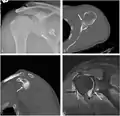

CT scan showing a bony Bankart lesion at the antero-inferior glenoid

MRI of the shoulder after an anterior dislocation showing a Hill-Sachs lesion and labral Bankart lesion